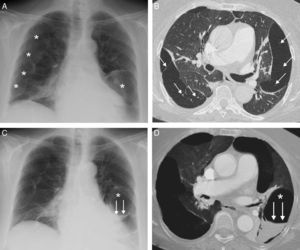

A) Radiografía de tórax en la que se observan múltiples formaciones quísticas subpleurales (asteriscos), en ambos pulmones. B) Imagen axial de la TC de tórax (ventana de pulmón) en la que se visualizan múltiples lesiones quísticas confluyentes en la periferia de ambos pulmones. Nótese la presencia de pequeños vasos pulmonares (flechas) que atraviesan las formaciones quísticas. C) Radiografía de tórax en la que se identifica la aparición de un nivel hidroaéreo (flechas) en una lesión quística de la base pulmonar izquierda (asterisco). D) Reconstrucción axial proyección de mínima intensidad (minIP), en la que se aprecia el nivel hidroaéreo (flechas) correspondiente al sangrado en el interior de una lesión quística (asterisco) del lóbulo inferior izquierdo.

Presentamos el caso de una hemorragia intraquística pulmonar secundaria a anticoagulación en una paciente no fumadora de 59 años con afectación pulmonar quística grave asociada a una EDCL. La paciente consultó por disnea progresiva y dolor torácico, y entre sus antecedentes personales destacaban, además de la enfermedad pulmonar quística secundaria a EDCL (para la que se encuentra en lista de espera para un trasplante pulmonar), un mieloma múltiple diagnosticado 8 años antes y un síndrome nefrótico refractario a tratamiento esteroideo secundario a la EDCL. Una radiografía de tórax (fig. 1A) demostró múltiples imágenes quísticas en ambos pulmones de predominio subpleural (ya conocidas). Una angiotomografía computarizada (angio-TC) de tórax detectó un tromboembolismo pulmonar (TEP), además de la presencia de grandes lesiones quísticas subpleurales de paredes finas en todos los lóbulos (descritas en estudios previos) atravesadas de vasos pulmonares (fig. 1B). Cuatro semanas después del inicio del tratamiento anticoagulante, la paciente presentó un episodio de dolor torácico izquierdo y un esputo hemoptoico, detectándose en la radiografía de tórax la aparición de un nivel hidroaéreo en la base pulmonar izquierda (fig. 1C). Una tomografía computarizada (TC) de tórax confirmó la presencia de un nivel hidroaéreo en el interior de una lesión quística del lóbulo inferior izquierdo (fig. 1D). La densidad elevada del componente líquido intracavitario sugería un sangrado reciente. Se procedió a embolizar con partículas de gelfoam las ramas arteriales pulmonares que rodeaban la formación quística sangrada, mejorando la sintomatología de la paciente.